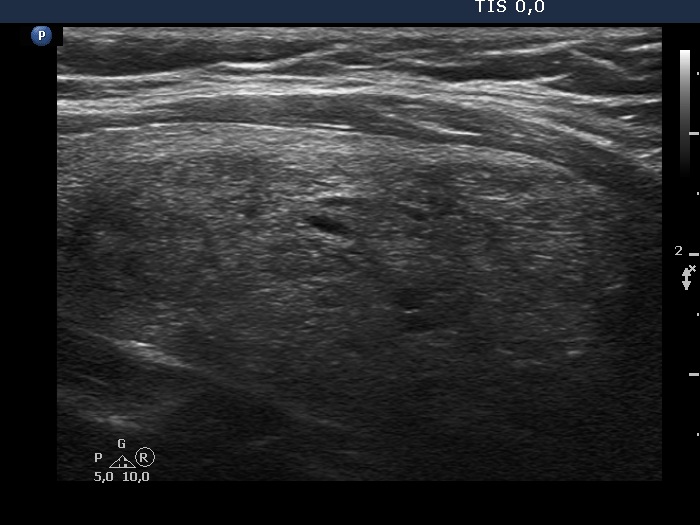

Study on 100 consecutive patients with thyroid nodule - case 067 (ultrasonographic picture 7)

Left lobe, longitudinal view. Although the length of the nodule exceeds 45 mm, the lobe is only minimally enlarged. The synchronous presence of echogenic lines and granules stands for the presence of connective tissue.